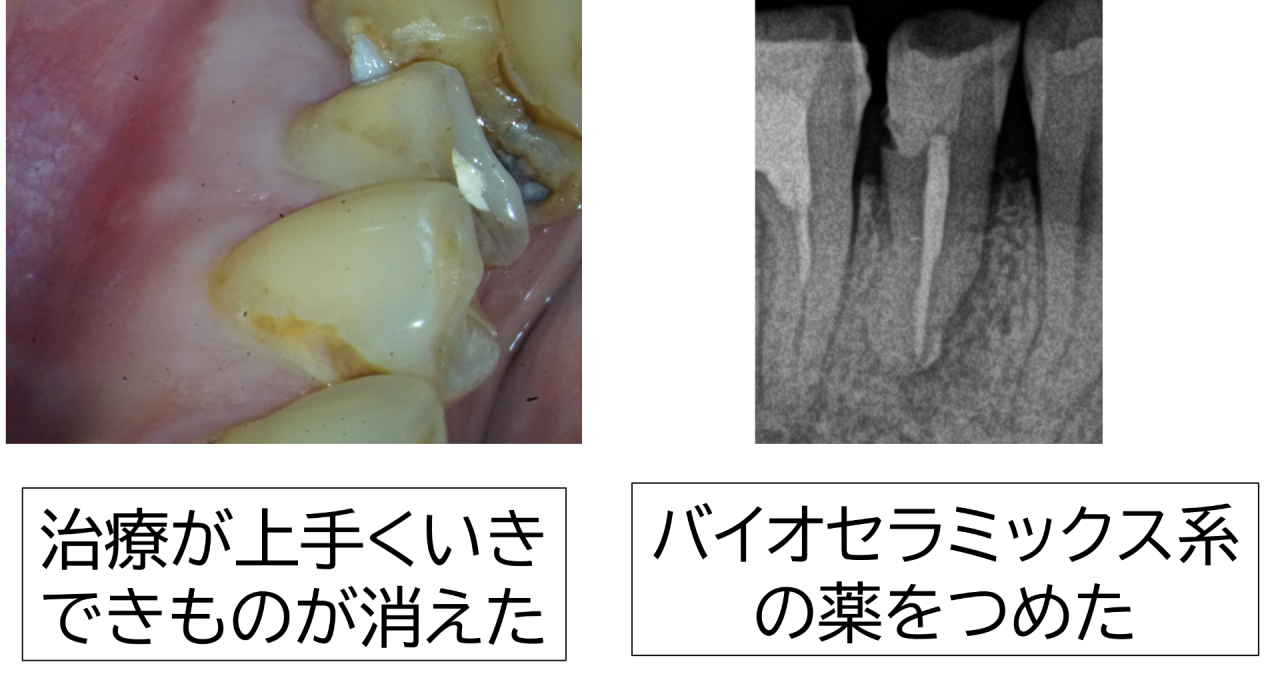

診察すると、過去に装着された銀歯が硬く、長年の噛み合わせによって歯の一部に細かいヒビや欠けが生じていました。その微細な隙間から虫歯菌が入り込み、二次的な虫歯が進行。レントゲン検査では虫歯が神経まで達し、歯の根の先端付近で炎症により顎の骨が大きく吸収している像が確認されました。いわゆる「骨が溶けている」状態です。感覚検査でも温刺激で強い痛みが長く続き、不可逆性歯髄炎の典型的な所見でした。歯ぐきにはできものもできており、骨が突き破られるほど進行していました。

症状が改善したのを確認後、ガッタパーチャとバイオセラミックス系(MTA系)のシーラーで根管をすき間なく封鎖し、細菌の再侵入を防ぎました。